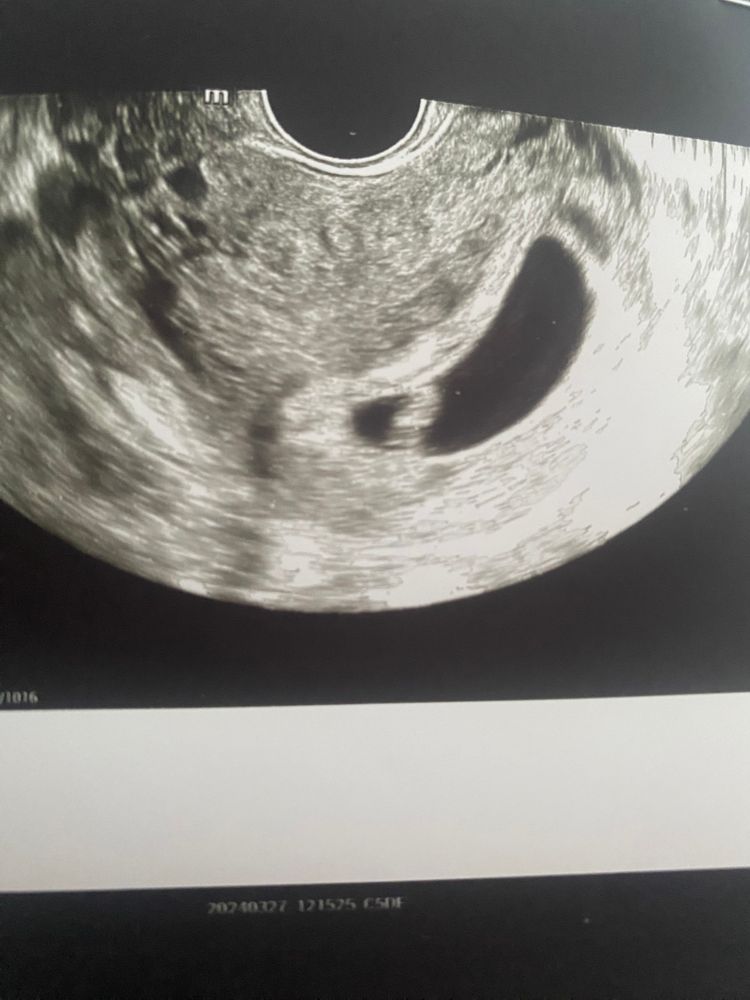

УЗИ 7.1 отслойка

Совсем крохотная отслойка. Вообще ни о чем.

Грозовой Фронт, вот не пойму что кровит(

Яна, отслойка и кровит.